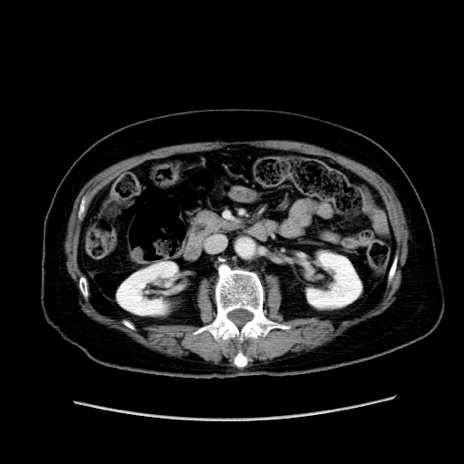

冠状断像

【症例】80歳代女性

【主訴】下腹部痛

【現病歴】約8時間前より下腹部痛の出現あり、救急外来受診。

【既往歴】両側付属器切除

【身体所見】意識清明、下腹部正中に手術痕あり、その部位に一致して圧痛と反跳痛あり。腸蠕動音は亢進。

【データ】WBC 9300、CRP 0.15